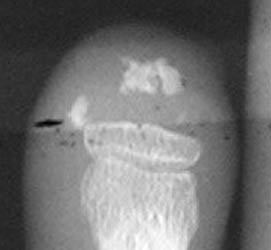

Radiographic Findings:

Acroosteolysis can occur due to resorptive changes at the distal phlangeal

tufts secondary to pressure from surrounding sclerotic soft tissues. The resorptive

process often causes a sharpening of the phalanx, known as "penciling".

The interphalangeal joints can also exhibit erosive changes; joint space narrowing

is usually a late stage finding. Occasionally tendon sheath fibrosis can cause

contracture deformities. Radiographic findings associated with the preferential

involvement of the 1st carpometacarpal joint can include osteolysis of the

trapezium and 1st metacarpal base, 1st metacarpal subluxation, and and intra-articular

calcifications. Soft tissue subcutaneous and periarticular calcifications

and soft tissue atrophy and thickening are common findings in scleroderma.